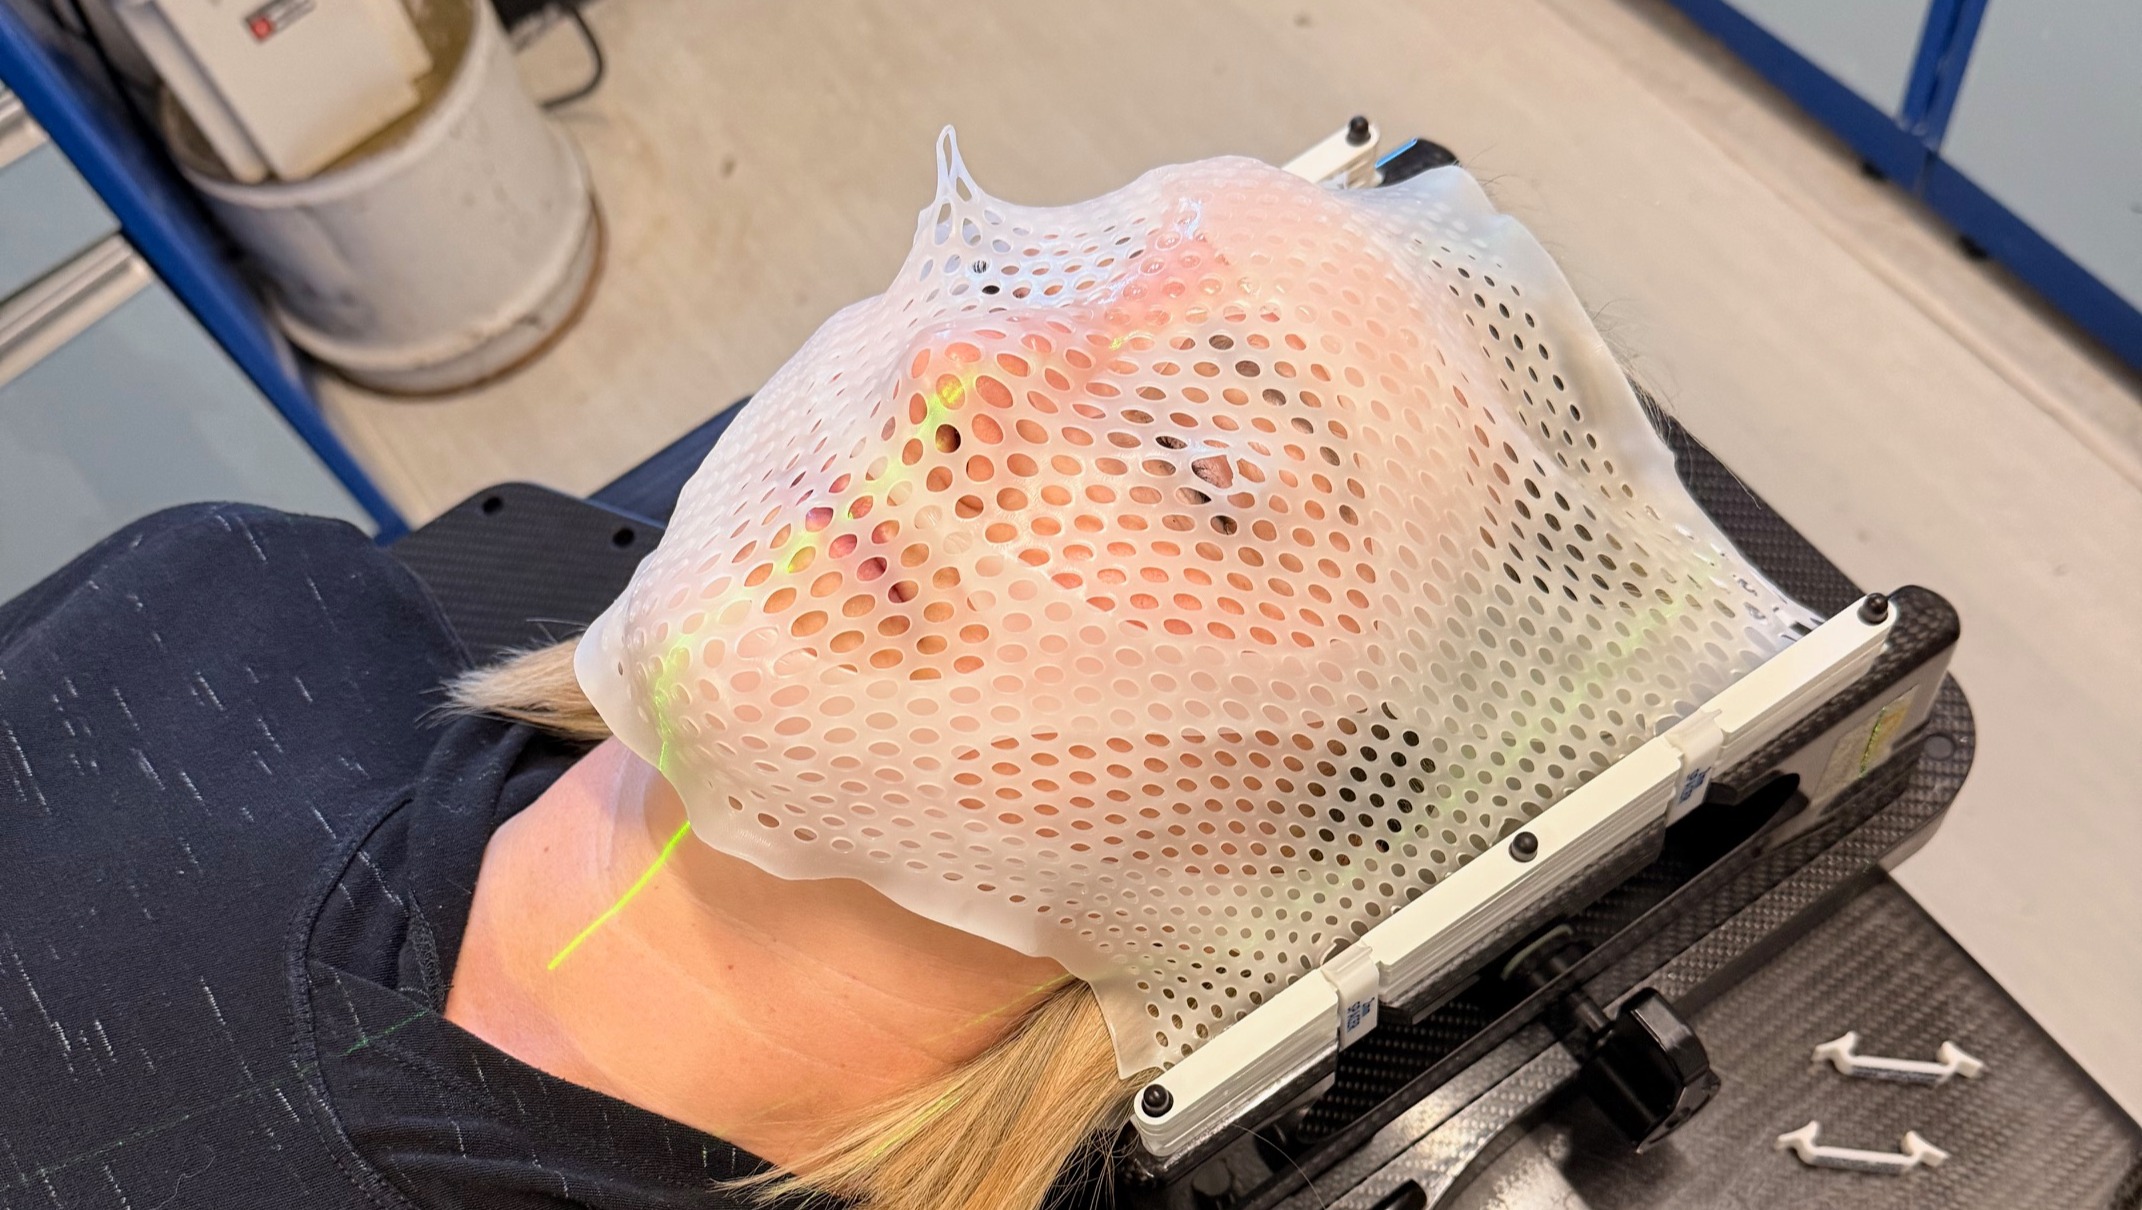

Katie undergoing intensive treatment to fight against cancer.

Mum fighting to be there for her boys